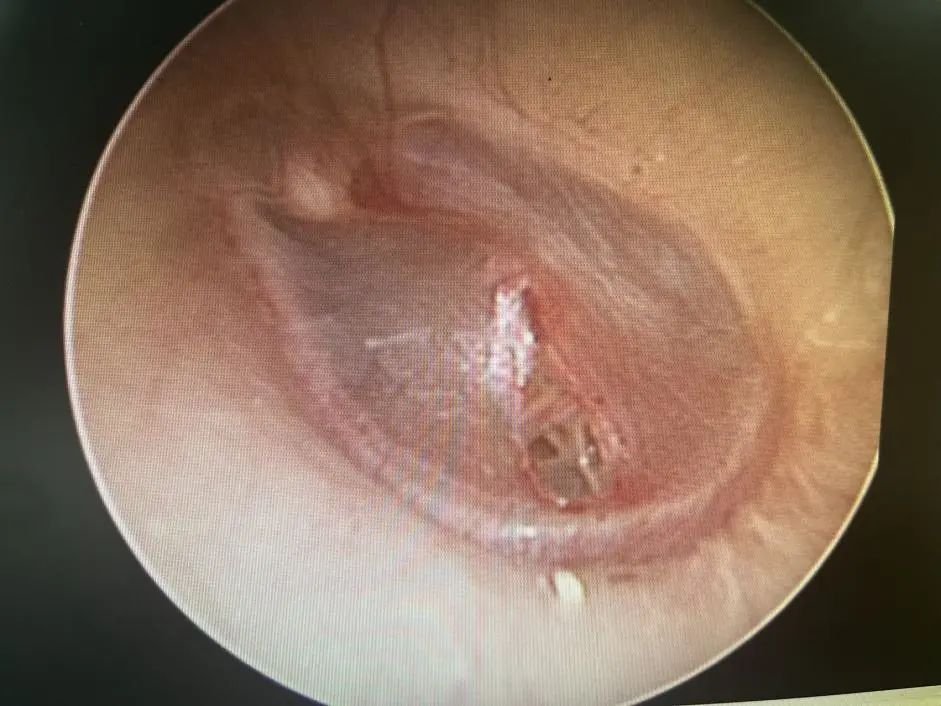

醫(yī)生在視頻耳內(nèi)鏡下發(fā)現(xiàn)左側(cè)鼓膜有一個破口,有血跡殘留在鼓膜上,還做了純音聽閾檢測,檢查結(jié)果顯示,小花的左耳聽力呈中度傳導性耳聾。

鼓膜穿孔